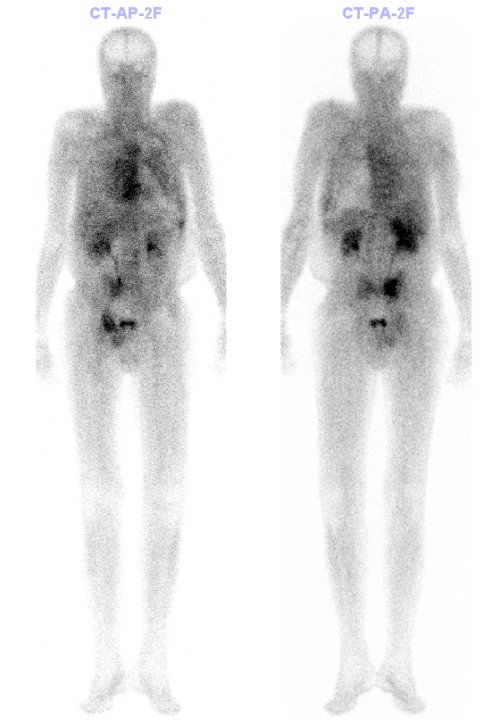

56letý pacient odeslán na vyšetření 3 fázové scintigrafie kostí k vyloučení meta procesu do skeletu. Vyšetření provedeno pomocí MDP značeného

99mTc z generátoru Ultratechnekow.

Ve fázi blood poolu patrný pleurální výpotek vlevo – traumatického původu.

Zvýšená perfuze a v kostní fázi zvýšená kostní přestavba patrná v rozsahu 2. až 8.

žebra levého hemithoraxu ventrálně a v distální části corpus sterní – v pravém SI kloubu a při pravém okraji křížové kosti, v horním i dolním raménku pravé stydké kosti – v.s. při čerstvých frakturách při laboratorně zjištěné osteoporoze těžšího stupně. Známky starších fraktur 11. žebra pravého hemithoraxu dorzálně, 9. a 10. žebra levého hemithoraxu dorzálně.

/ Obr. č. 2: Celotělová třífázová scintigrafie skeletu v kostní fázi.